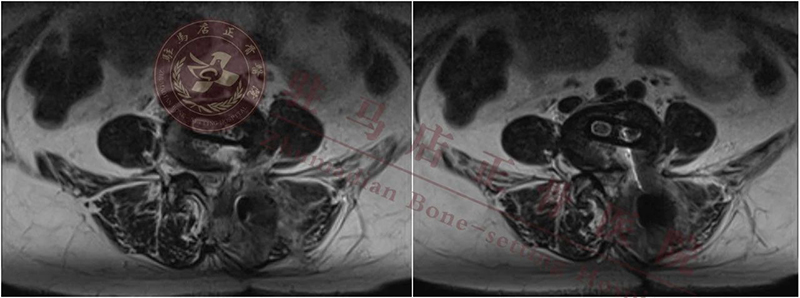

【诊 断】:1.腰椎管狭窄症(L4/L5); 2.腰椎间盘突出症(L4/L5); 3.腰4椎体滑脱(II度)

【术前计划】:通过影像等相关检查,明确诊断,根据诊断确定手术方式:经内镜下行腰4/5椎间盘切除、椎管扩大减压、椎间植骨融合复位、经皮椎弓根螺钉单侧内固定术

植入cage

cage横打的位置

➢ 术前要测量数据引入术中,术中测量安全范围,充分保护硬膜及出、行走神经

➢ 充分暴力安全三角范围,根据术中测量数据选择大的cage

➢ 术中终板处理要求严格,要尽量往对侧处理